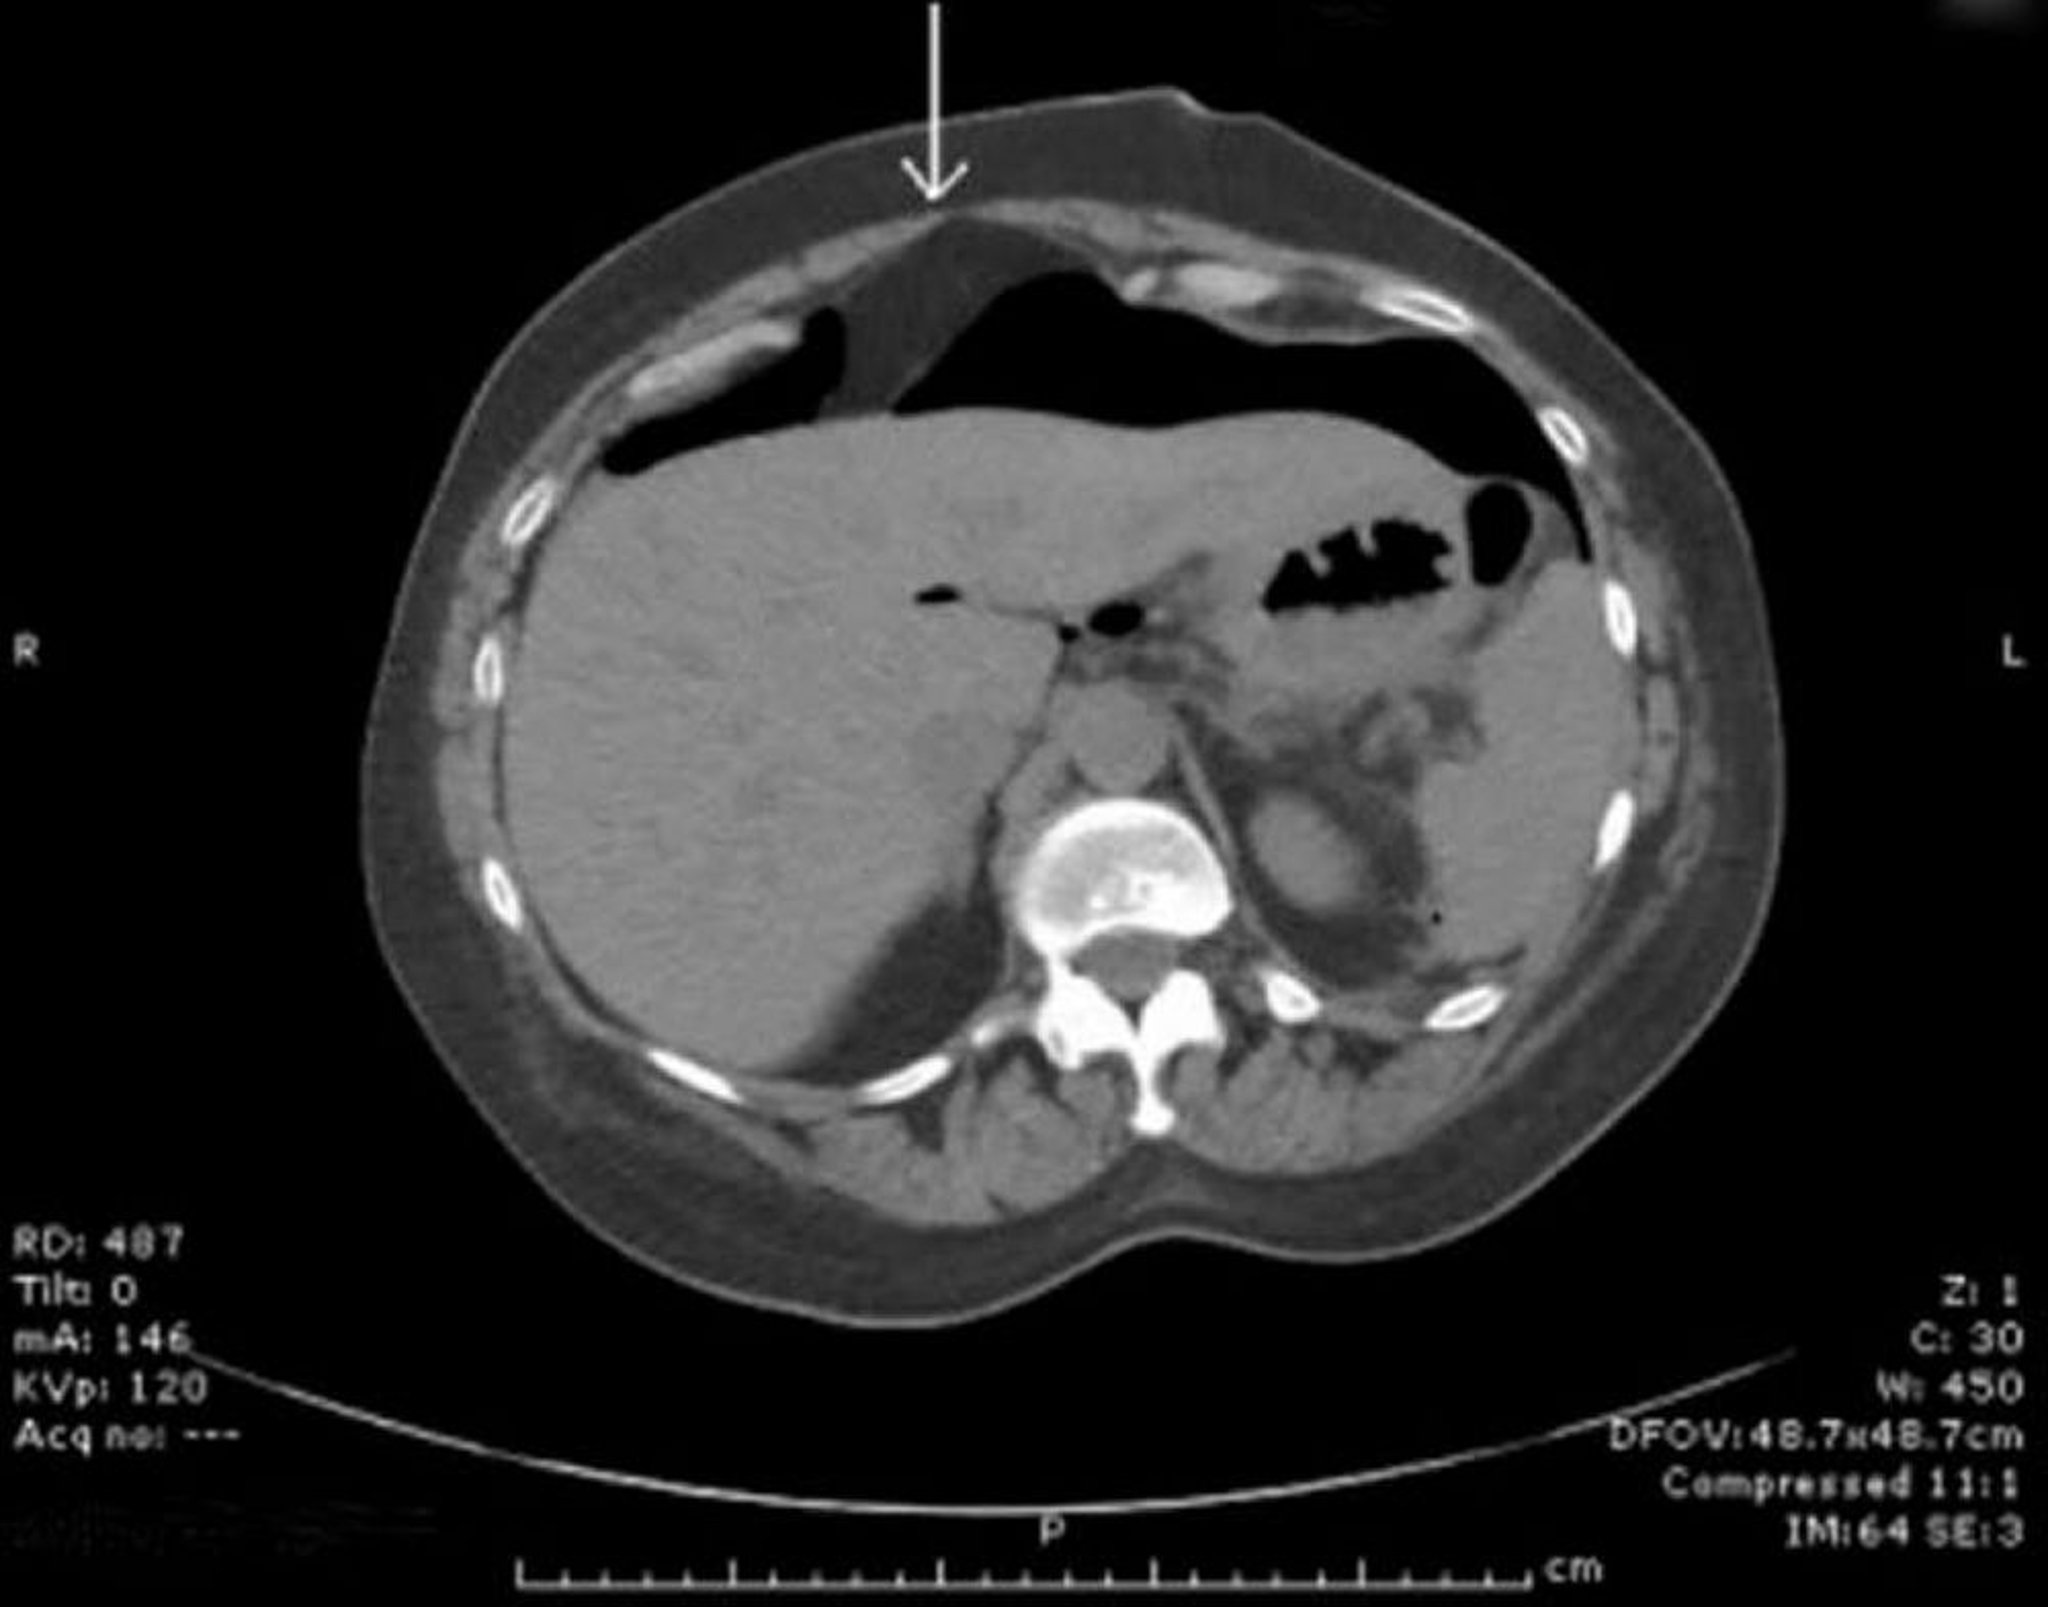

TC com ar livre na cavidade peritoneal

Ar livre é visto anteriormente ao fígado. A seta indica o ligamento falciforme.

Image provided by Parswa Ansari, MD.